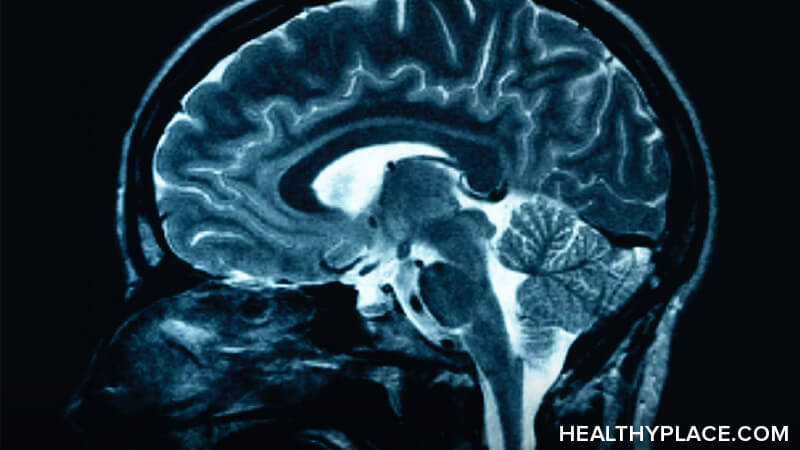

其他研究由NIMH研究人员进行,使用成像技术研究与ADHD和非ADHD男孩的男孩的大脑结构。这些研究指出了结构脑差异作为ADHD可能的贡献原因。数据显示,ADHD男孩的大脑具有比普通男孩的大脑更具对称的结构。尽管对称性较大,但ADHD大脑具有较小的前额叶皮质皮质,尾状核和Globuspallidus。科学家指的是前额皮质作为大脑的指挥中心,另外两种结构将命令转化为导致行动的思想。